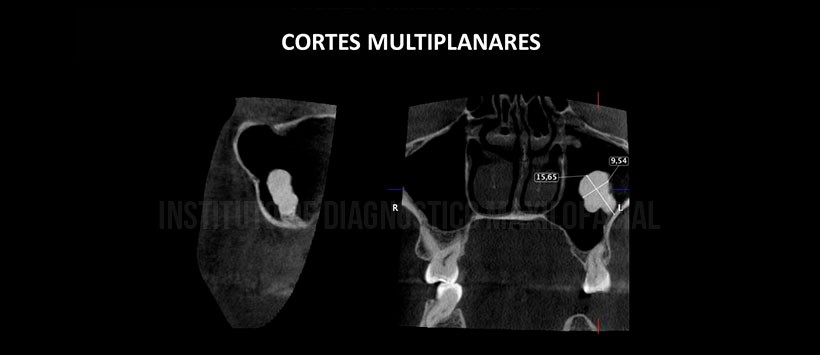

A la evaluación de la tomografía volumétrica (CBCT) en cortes multiplanares (Figura 2), axiales (Figura 3), se observa imagen hiperdensa de densidad de hueso cortical, forma irregular, límites definidos, de apariencia “pediculada” en contacto con el contorno de las paredes anterior y posterior del seno maxilar izquierdo. Presenta una dimensión de 15.65×9.54mm y de un volumen de 0.765cm3 (Figura 4).